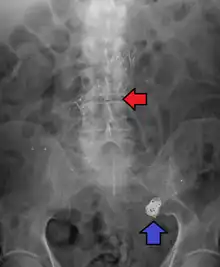

Ruptured 7mm left vertebral artery aneurysm resulting in a subarachnoid hemorrhage as seen on a CT scan with contrast

Diagnosis of a ruptured cerebral aneurysm is commonly made by finding signs of subarachnoid hemorrhage on a computed tomography (CT) scan. If the CT scan is negative but a ruptured aneurysm is still suspected based on clinical findings, a lumbar puncture can be performed to detect blood in the cerebrospinal fluid. Computed tomography angiography (CTA) is an alternative to traditional angiography and can be performed without the need for arterial catheterization. This test combines a regular CT scan with a contrast dye injected into a vein. Once the dye is injected into a vein, it travels to the cerebral arteries, and images are created using a CT scan. These images show exactly how blood flows into the brain arteries.